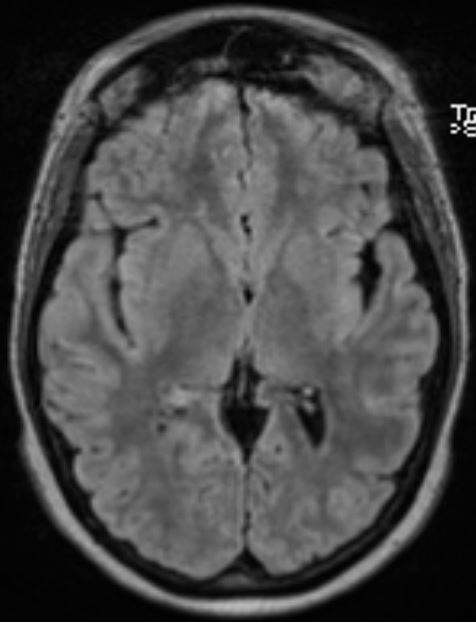

The structural correlates of the above EEG findings appear below. There is enlargement of the left-ventricular system, atrophy of the head, body and tail of the caudate nucleus and the left hemisphere appears modestly smaller in size than the right, most evident on axial sequences. The MRI was done while the patient was quite restless. As you can see from these pictures, the left occipital cortex and the left thalamus do not demonstrate any structural correlate to the asymmetry of alpha rhythms. However, we know from the EEG that the left hemisphere is markedly dysfunctional. Unsurprisingly, on functional MRI scans language is represented in the right hemisphere.